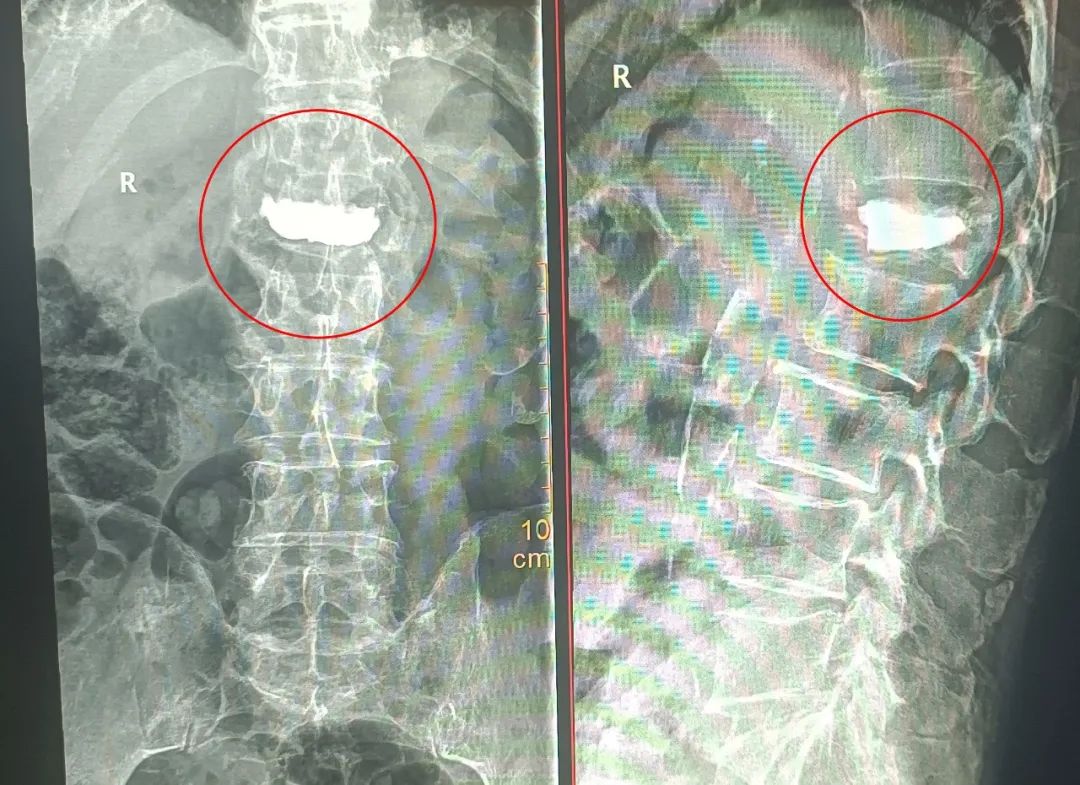

为了使张爷爷得到更舒适化的治疗,入院后,骨二科科室主任柯贤明主任医师与丁志敏副主任医师综合病史、查体及完善相关检查,组织手术团队进行详细讨论分析,在充分沟通并取得患者及家属同意后,骨二科手术团队在麻醉科的积极护航下,为患者行「全麻下胸腰椎骨折内固定+病椎椎体强化治疗」,手术过程十分顺利。